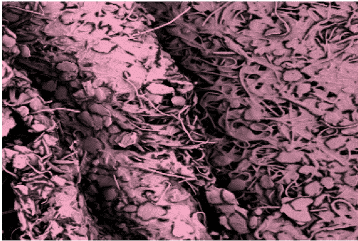

- The Phoenix Wound Matrix®, a fully resorbable, 3D electrospun device composed of synthetic polymers, is designed to provide a temporary microenvironment that supports endogenous wound healing, allowing for regeneration and remodeling of native tissue in the defect space/wound bed. This device is engineered to promote healthy tissue growth rather than a protracted inflammatory response.†

- For over a decade, Nanofiber Solutions, the technical parent company of RenovoDerm®, has worked with progressive surgeons and researchers to develop products designed to mimic the in vivo, microscopic, physical structures and properties of the extracellular matrix (ECM) vital to functional tissue regeneration.